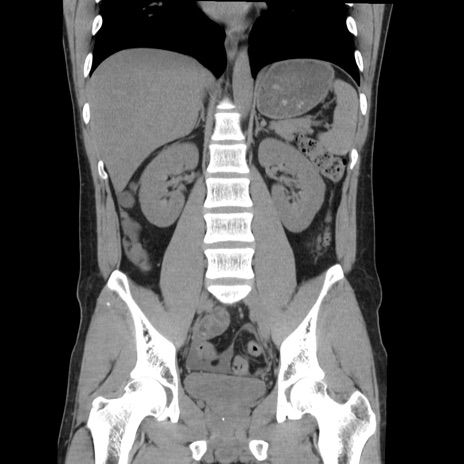

症例36(冠状断像)

【症例】20歳代 男性

【主訴】心窩部痛

【現病歴】今朝より上腹部痛あり。一旦軽快していたが再度出現したため救急要請。昨日夕に白身の魚を含む刺身を食べた。

【身体所見】BP 136/89mmHg、HR 74/min、BT 37.0℃、腹部:膨満、軟、心窩部に圧痛あり。反跳痛なし、筋性防御なし、腸雑音やや亢進あり。

【データ】WBC 17700、CRP 0.48